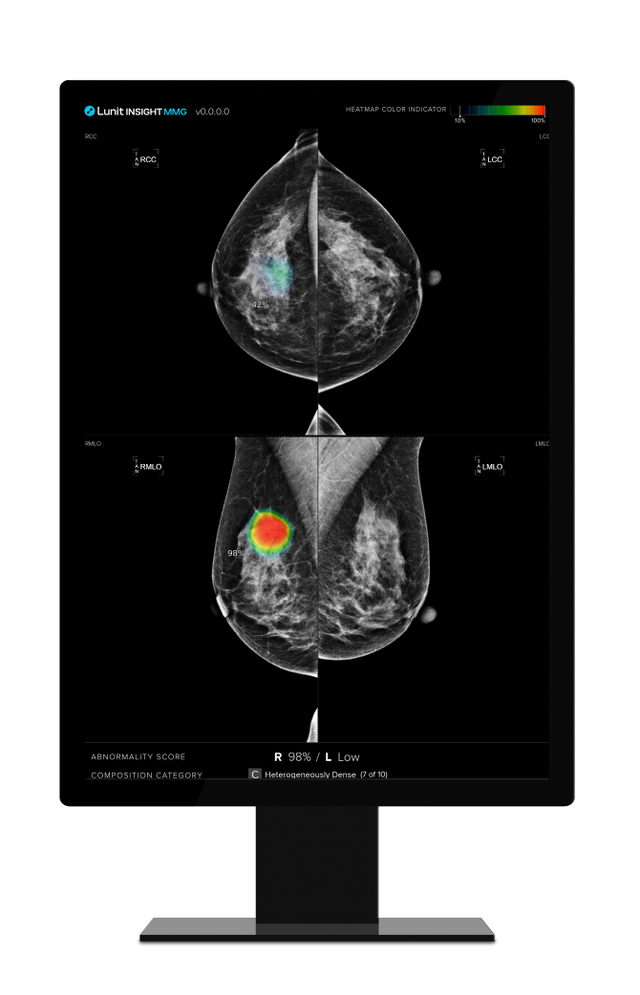

Lunit INSIGHT MMG. ⓒ 루닛

[프라임경제] 의료 인공지능(AI) 기업 루닛(328130)은 유방 촬영술 인공지능(AI) 영상분석 솔루션 '루닛 인사이트 MMG'의 유방암 조기 발견 및 의료진 업무 경감 효과를 입증한 유럽 연구 2건이 세계적 권위의 의학 저널에 게재됐다고 23일 밝혔다.

AI는 각 유방에 0부터 100까지의 점수를 부여하는데, 점수가 높을수록 유방암 가능성이 높음을 의미한다. 연구 결과, 나중에 암이 발견된 유방과 그렇지 않은 반대쪽 유방 사이의 평균 AI 점수 차이가 시간이 지남에 따라 증가했다.